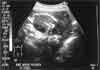

Bay's Photo Diary - June 2001

doctor's checkup

a few hours new